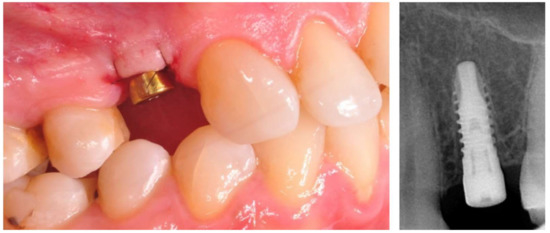

2.4. Surgical Phase

Figure 1. Implant with the healing abutment placed in bicuspid region and left for open healing.